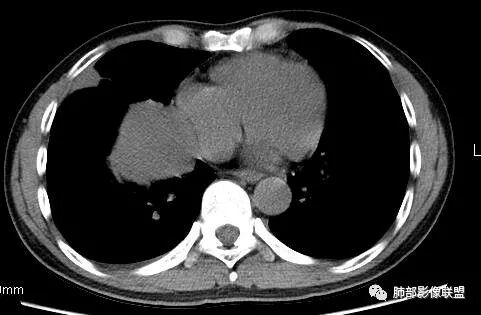

5.病灶密度大多不均,不规则坏死液化,少数病例出现钙化。增强扫描常观察到由外而内的厚壁不均匀强化,中央半岛样强化等等,厚壁中或实性区常能显示血管影。一些病灶中央呈现边界清楚囊样变。

6.病灶侵犯胸膜时可以出现胸水,病灶可以侵犯胸壁并引起相应临床症状。

3.PPS在肺实质内成膨胀性生长,很少侵犯或突破支气管黏膜,影像学表现密度均匀、边缘光整的肿块,少有空洞、分叶、毛刺、钙化,一般为单发,体积较大,直径多在4cm以上,增强后呈不均匀强化。